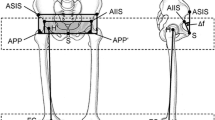

The studies were acquired on a General Electric 9800 CT scanner (Milwaukee, WI, USA) with Hilite detectors. Images were attained at 3-mm contiguous intervals of 3-mm thickness [42] or 5-mm intervals for patients older than 16 years as per the radiologists’ protocol. The technique used was 120 kVp and 40 to 80 mA, depending on the patient’s size. These parameters were chosen to yield a study of sufficient quality yet minimize radiation exposure. Images were stored on magnetic tape or optical disk and transferred to a free-standing computer workstation (Sun Microsystems, Palo Alto, CA, USA). The 3-D volume images and 2-D planar reformatted images were created and analyzed using ISG Allegro multimode rendering software (ISG Technologies [renamed Cedara], Mississauga, Ontario, Canada). Before any measurements, the 3-D pelvic images were reoriented into the anatomic position with both anterosuperior iliac spines in the same transverse plane and in the same coronal plane as the pubis [44, 51]. One author (HvB) performed all image orientations and measurements in a nonblinded manner.

A CT scan shows a subject who has bilateral nondysplastic hips. (A) A reformatted coronal section was taken from the scan through the midacetabulum. The space between the acetabulum and the femoral head is highlighted. The pelvis is positioned anatomically. (B) Three-dimensional acetabular fills were created from the same scan after bony elements were removed. The pelvis is positioned anatomically.

Reformatted images were acquired from the 3-D CT of a nondysplastic right hip. (A) The acetabular fill rotated into profile (rotating the acetabulum to a 0° anteversion position) displaying the parameters of length and depth. Length is the longest straight-line distance in the coronal plane. Depth is the greatest perpendicular distance from the acetabular opening plane to the medial acetabular wall. (B) The parameter of width is displayed on a transverse section through an anatomically positioned right acetabulum at the level of the acetabulum’s greatest width. (C) A perspective showing a left hip acetabular fill with the opening facing directly toward the viewer. The acetabular width is indicated. The pelvis tilt was corrected to bring the pelvis into the anatomic position. (D) A transverse section is made through the anatomically positioned right acetabulum at its greatest width. The acetabular anteversion is the angle between the sagittal plane of the pelvis and a line connecting the anterior and posterior margins of the acetabulum at this level. (E) A dysplastic left hip acetabular fill-in was rotated into a profile (rotating the acetabulum to a 0° anteversion position). Anteversion is measured at the widest level of the acetabulum. Torsion 1 is measured at the junction of the first and second quarters, Torsion 2 is measured at the junction of the third and fourth quarters. By comparing figure E, a dysplastic acetabular fill, with Fig. 1B, a nondysplastic acetabular fill, the more elongated and torsioned morphology of the dysplastic acetabulum becomes evident.

Opening plane abduction angle was measured as the acute angle between the acetabular opening plane and the transverse plane of the pelvis. For this measurement, the acetabular fill was viewed in direct profile by rotating the acetabular opening plane until it was perpendicular to the coronal plane (0° anteversion position) (Fig. 4A). In the case of an acetabulum that was truly a half sphere, the acetabular position in space could be precisely described by the acetabular anteversion and the opening plane abduction angle.

(A) A nondysplastic left hip acetabular fill was rotated into a profile (rotating the acetabulum to a 0° anteversion position). The opening plane abduction angle is the acute angle between the acetabular opening plane and the transverse plane of the pelvis. (B) The same acetabular fill demonstrates the roof angle. The roof angle is measured as the angle between the transverse plane and a line connecting the superolateral corner and the deepest point of the acetabulum.